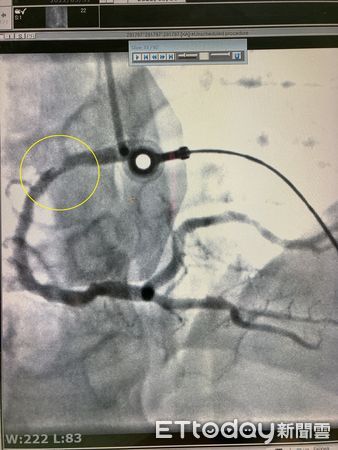

▲南投醫院醫師賴昭宏指出患者右側冠狀動脈近端阻塞。(圖/衛福部南投醫院提供)

▲黃圈處為血管栓塞處。(圖/衛福部南投醫院提供)

38歲吳姓男子日前騎機車上班,途中突被蜜蜂叮咬眼皮,到班後除感覺疼痛,還全身起紅疹,同事趕緊將他送急診;醫師先針對蜂螫過敏反應給予治療,但吳男又表示胸痛,進一步檢查診斷竟為急性心肌梗塞,立即安排心導管手術,發現右側冠狀動脈近端阻塞,經血管支架放置在狹窄部位後,現已康復出院,將持續門診追蹤治療。

南投醫院心臟內科醫師賴昭宏認為,吳男平時有抽菸、體重較重,並罹患三高等慢性疾病,上述因子導致血管較狹窄,彈性也較差,血管內逐漸形成斑塊,因尚有足夠血液量供應心臟,未有明顯不適;但當天氣溫差大、遇到壓力或像這次蜂螫等刺激時,便可能誘發斑塊破裂剝落,引起血栓堵塞血管,發生致命的心肌梗塞。